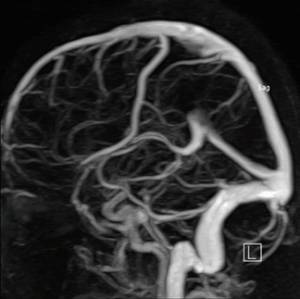

Врачи отмечают, что ангиография сосудов мозга является важным инструментом в диагностике различных заболеваний. Этот метод позволяет визуализировать кровеносные сосуды, выявляя аномалии, такие как аневризмы, стенозы и тромбы. Специалисты подчеркивают, что ранняя диагностика этих состояний может значительно повысить шансы на успешное лечение и предотвратить серьезные осложнения, включая инсульт.

По способу получения данных ангиография сосудов головного мозга может быть традиционной рентгеновской, компьютерной (основанной на рентгеновских снимках) и магниторезонансной.

С помощью специального катетера в кровеносное русло вводится контрастное вещество. После этого выполняется серия рентгеновских снимков церебральных сосудов.

Эти снимки демонстрируют различные фазы кровообращения: капиллярную, артериальную и венозную. Современные медицинские технологии позволяют получать послойные изображения, которые затем обрабатываются с помощью специализированных компьютерных программ для создания трехмерной модели.

- Возможность создания трехмерной модели,

- Визуализация сосудов, которая помогает врачу выявить тромбы, гематомы и аневризмы,